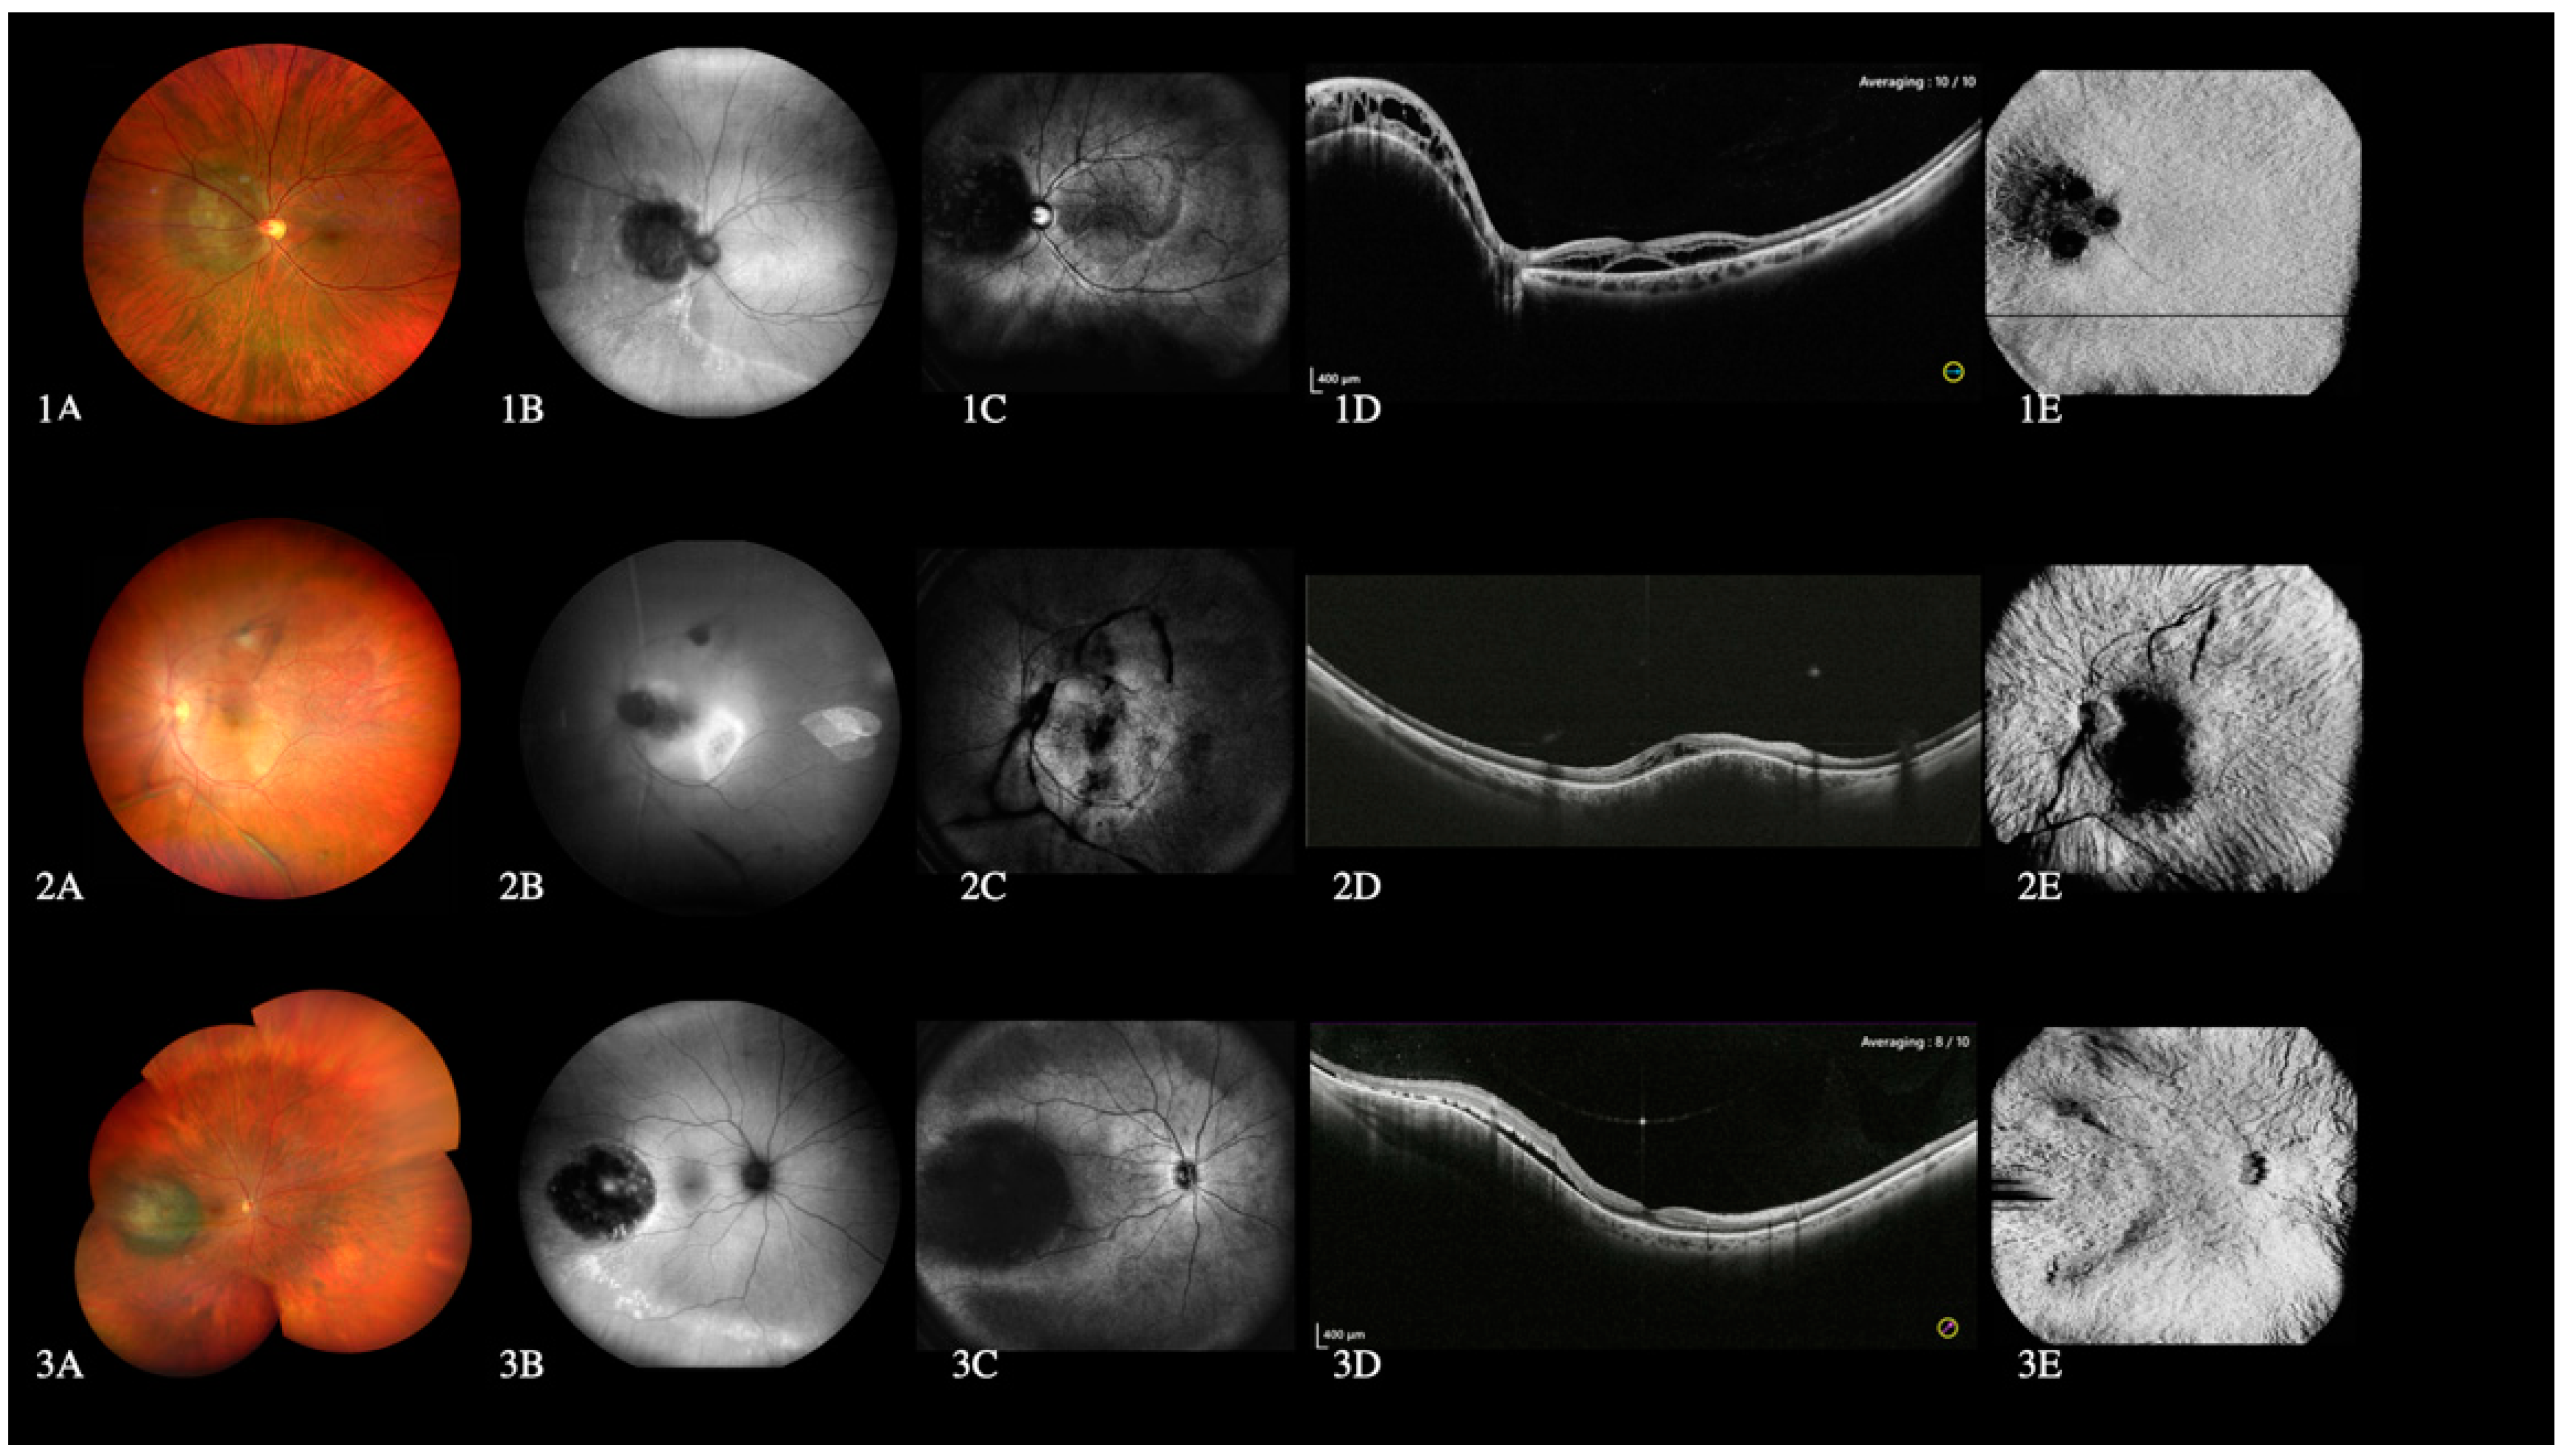

3.5. Choroidal Lesions

4.4. Choroidal Lesions